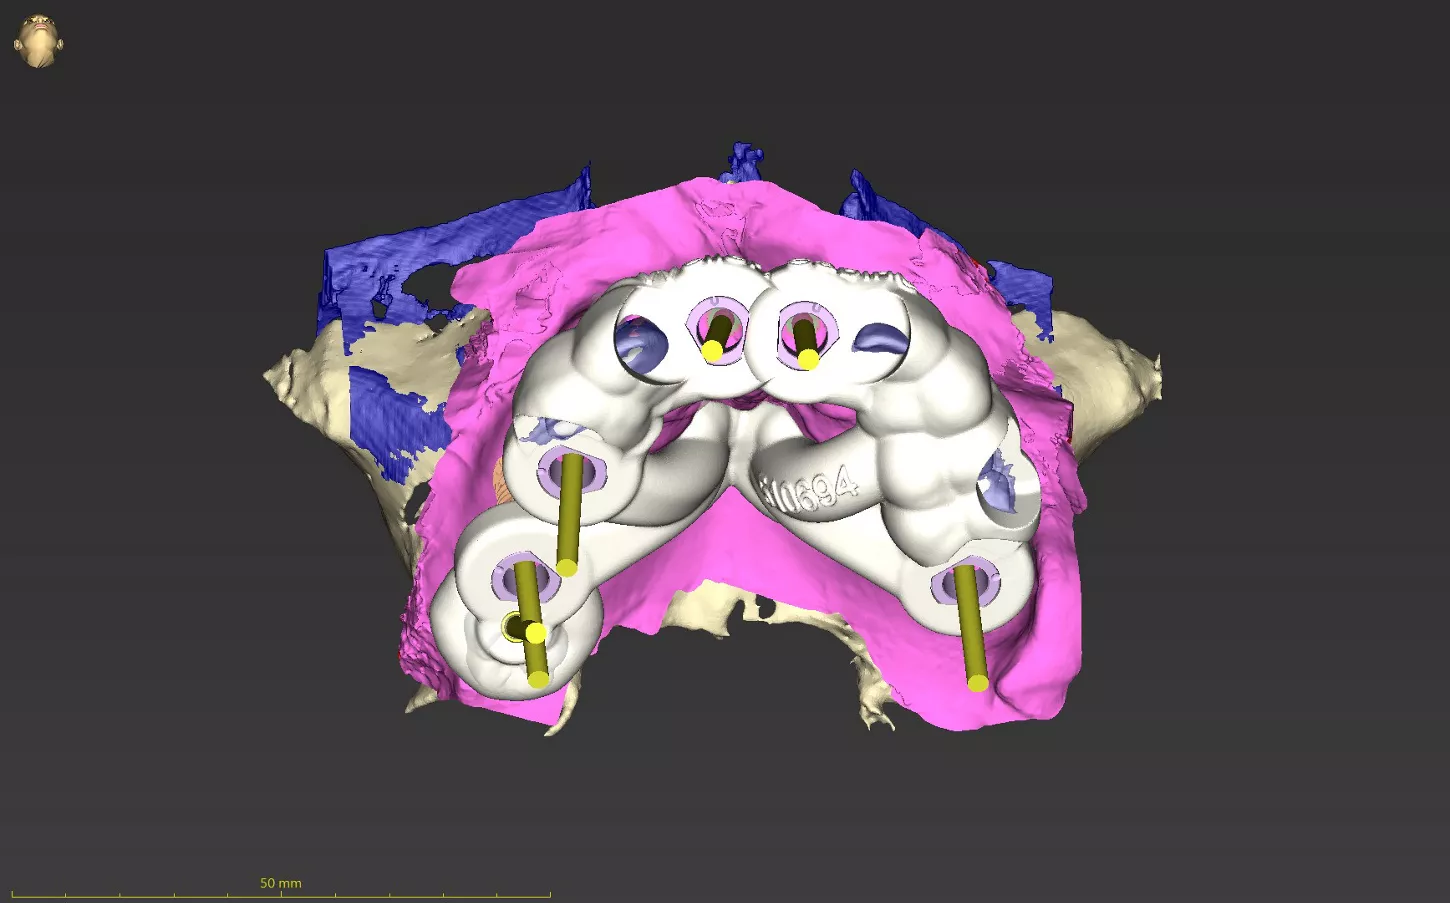

3. Plan of full guided workflow: implant alignment, sleeve placement and surgical drill guide design in coDiagnostiX®.

6. Representation of implants used; lower jaw, four Axiom X3® Tissue Level Narrow platform implants of gingival height 2.5 mm in Ø3.4 mm and Ø4.0 mm. Upper jaw, Axiom X3® Bone Level Ø3.4 mm and Ø4.0 mm.